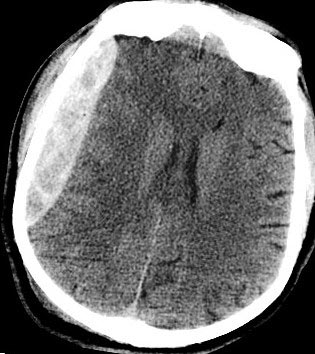

A CT scan of the head showing a large blood clot after a head injury - epidural hematoma.

Note: Images are shown for illustrative purposes. Do not attempt to draw conclusions or make diagnoses by comparing these images to other medical images, particularly your own. Only qualified physicians should interpret images; the radiologist is the physician expert trained in medical imaging.